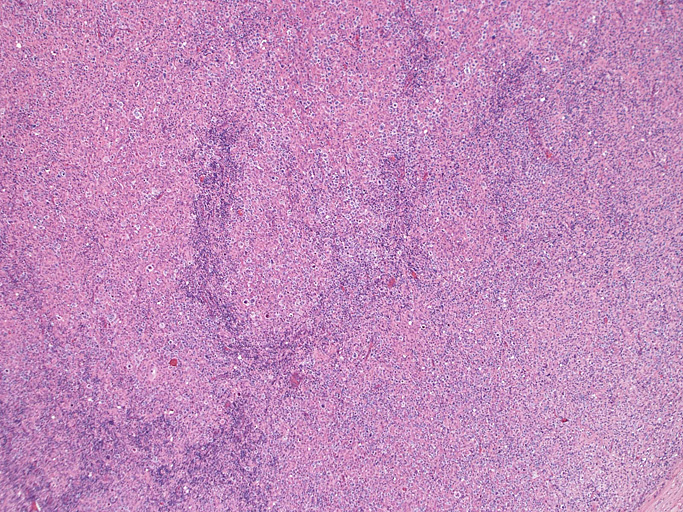

直径17mmの腫大したリンパ節。被膜は軽度線維性肥厚を示す。リンパ節の基本構造は失われ不明瞭な結節様構造が集蔟しているように見える。

光顕および免疫染色所見

結節構造内では, 好酸性細胞質をもつ組織球の増生を背景に大型異型細胞が散在性または集蔟して増殖している。被膜下にも線維化組織内にbizzarreな大型細胞が認められる。リンパ球は小型リンパ球が大型異型細胞を含む組織球性の結節辺縁に存在する。大型細胞は, centroblastic cellが多く, その他 Hodgkin cell-like cell, RS細胞様巨細胞, 腎臓型の核をもった細胞, 多型核の細胞など多彩な形態を示す。異型核分裂像をふくむ核分裂像が多い。